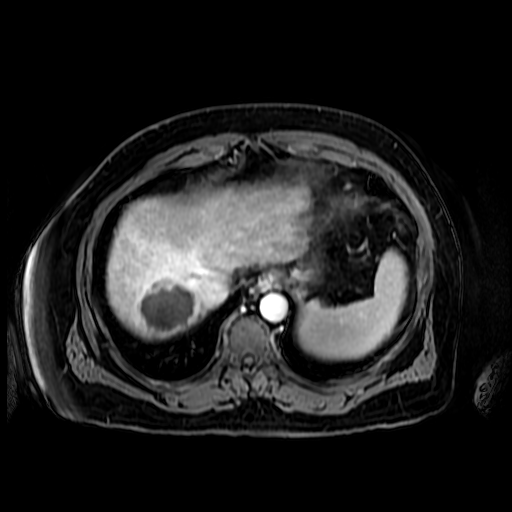

His intention for retirement was to decompress, spend time with his beautiful wife, Lorraine, his children and grandchildren. However, during a routine exam, an MRI was ordered in November 2022 which revealed he had a tumor measuring 5.1 cm in size. Another MRI in February 2023 found it had grown to 5.6 cm! We were informed by his medical team at Jefferson Health that Radioembolization (Y90) would be the next course of action and it was scheduled for March 2nd, 2023. This procedure was expected to decrease the size of the tumor up to 70%. The radiation was taxing on my Dad, and he struggled with many adverse effects during the following months. On April 20th another MRI with contrast was performed and found the tumor had not shown the shrinkage we had hoped for. The next step is a follow up MRI on June 20th.